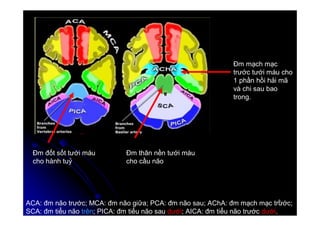

Đm đốt sốt tưới máu

cho hành tuỷ

Đm thân nền tưới máu

cho cầu não

Đm mạch mạc

trước tưới máu cho

1 phần hồi hải mã

và chi sau bao

trong.

ACA: đm não trước; MCA: đm não giữa; PCA: đm não sau; AChA: đm mạch mạc trước;

SCA: đm tiểu não trên; PICA: đm tiểu não sau dưới; AICA: đm tiểu não trước dưới.

1. ĐM tiểu não dưới:

. Sau (PICA có màu xanh blue).

. Trước (AICA có màu hoa cà).

2. ĐM tiểu não trên (SCA có màu trắng).

Lát cắt thấp hơn Lát cắt cao hơn